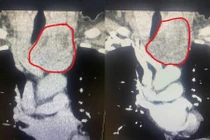

Lấy u tuyến giáp thòng xuống trung thất không cưa xương ức

U tuyến giáp kích thước lớn nếu không được phẫu thuật điều trị kịp thời có thể gây ra các biến chứng về xương khớp, tim mạch, huyết áp, đột quỵ...

Ngày 1/7, Bệnh viện Đa khoa Hùng Vương cho biết đã tiếp nhận và phẫu thuật thành công cho một bệnh nhân bị bướu giáp thòng trung thất. Đây là một ca bệnh được đánh giá có mức độ khó cao, thường phải chuyển tuyến trên, với triệu chứng nghẹn cổ, khó thở, đặc biệt khi nằm ngửa.

Bệnh nhân là cô Ma.Thị.T. (sinh năm 1974). Thời gian gần đây, bệnh nhân nhận thấy vùng cổ xuất hiện khối bướu ngày càng to, kèm cảm giác nghẹn và khó thở. Khi đi thăm khám tại một cơ sở y tế, phát hiện có khối bướu giáp lớn thòng xuống trung thất, được tư vấn đây là ca bệnh phức tạp, cần chuyển tuyến trên để xử trí.